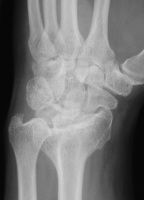

Three months postop :

Image Image Image